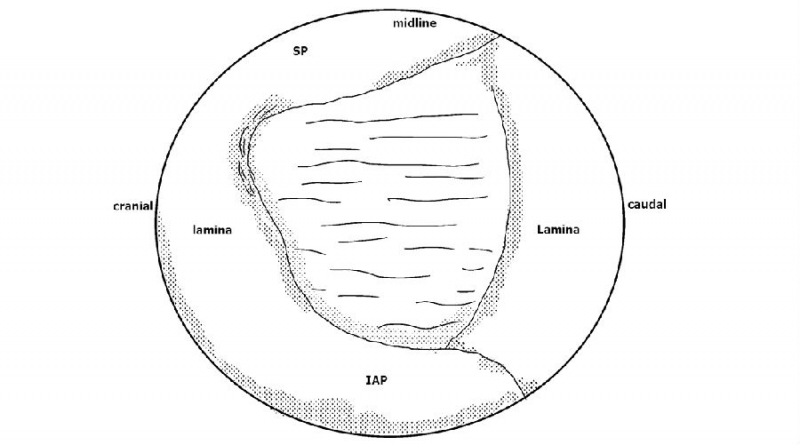

1. 建立通道后的多裂肌三角“地板解剖”;

2. 大刀头清理软组织;